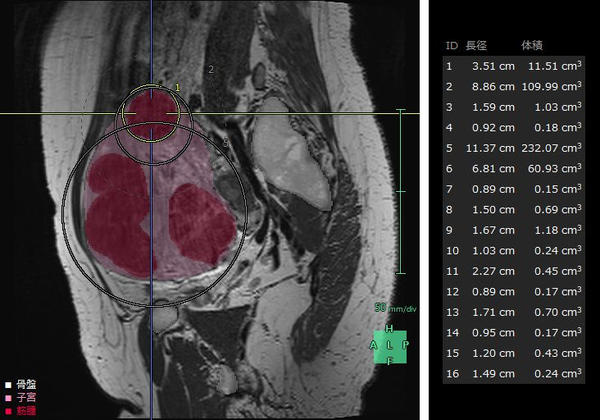

(1)婦人科臓器解析

子宮筋腫は,成人女性の罹患率が20~30%と高頻度に見られる疾患*4で,機能温存が重要とされている。MRIや超音波画像診断装置の2D画像では筋腫や周囲組織の3次元的な把握が難しく,骨盤内の複雑な解剖構造の理解も困難。また,筋腫の大きさや数,妊孕性温存の希望などにより様々な手技が適用されるが,筋腫の計測や手技の選択は各医師の経験則や感覚に基づいて行われているという課題がある。「婦人科臓器解析」ではMRIのT2画像からAI技術*2を活用した抽出エンジンを用いて子宮周囲の臓器をセグメンテーションし,ユーザーが子宮筋腫と判断した箇所の体積・数・深さの定量化を行うことができる。また,3Dで周辺組織との位置関係を把握することで筋腫手術の低侵襲化や取り残し防止等への寄与が期待される。

婦人科臓器解析の解析画面